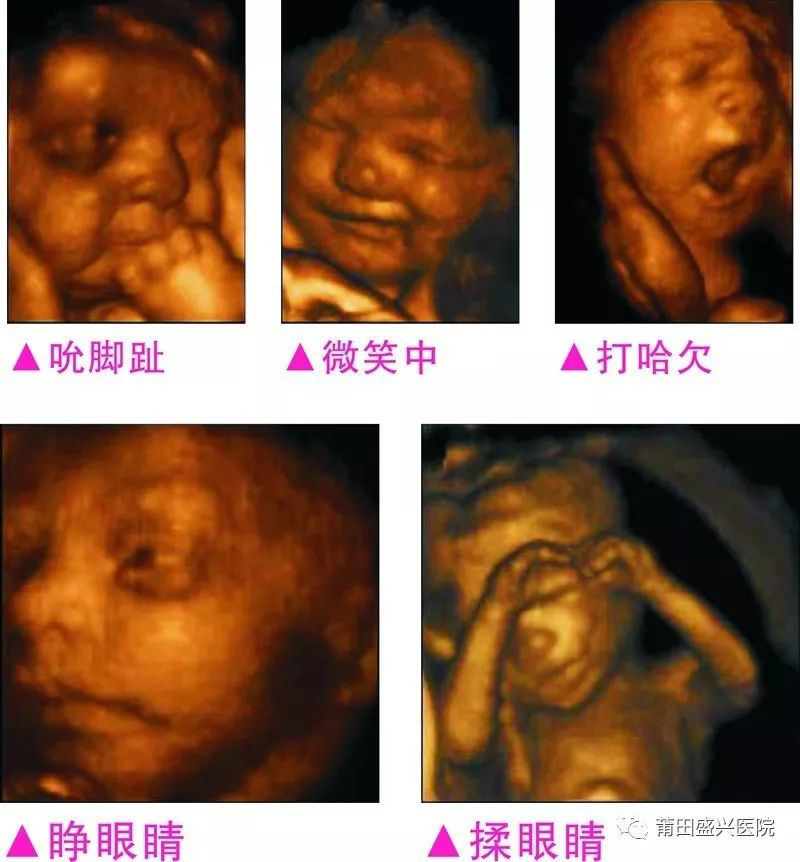

您一定不知道寶寶有多調皮可愛

你一定不知道寶寶這么小就有這么多表情

四維容積成像技術,智能光源系統(tǒng)展現梯度亮度,渲染畫面,提高容積成像品質,高清顯示腹中寶寶的實時動態(tài)影像,完整記錄寶寶的一舉一動,讓準爸媽與寶寶Di一次幸福“見面”,更可刻錄成高清視頻,送給未來寶寶的珍貴禮物。